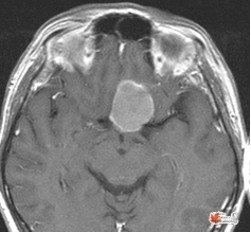

Where are structural or functional abnormalities that can cause an altered state of consiousness?